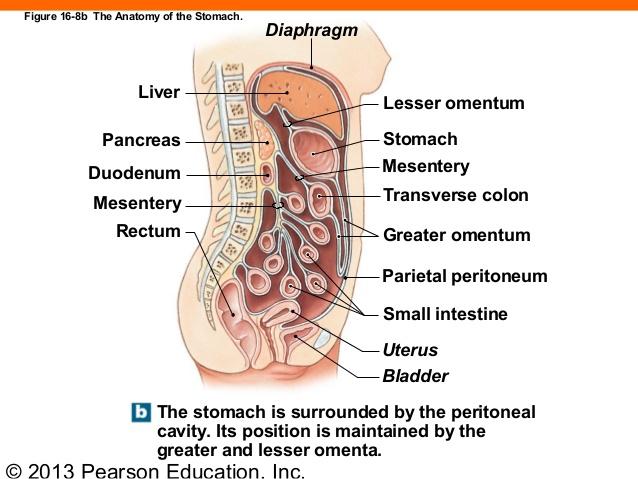

Serous membranes

...

2

Parietal Peritoneum

3

Dorsal Mesentery

4

Visceral Peritoneum

5

Lesser Omentum

6

Greater Omentum